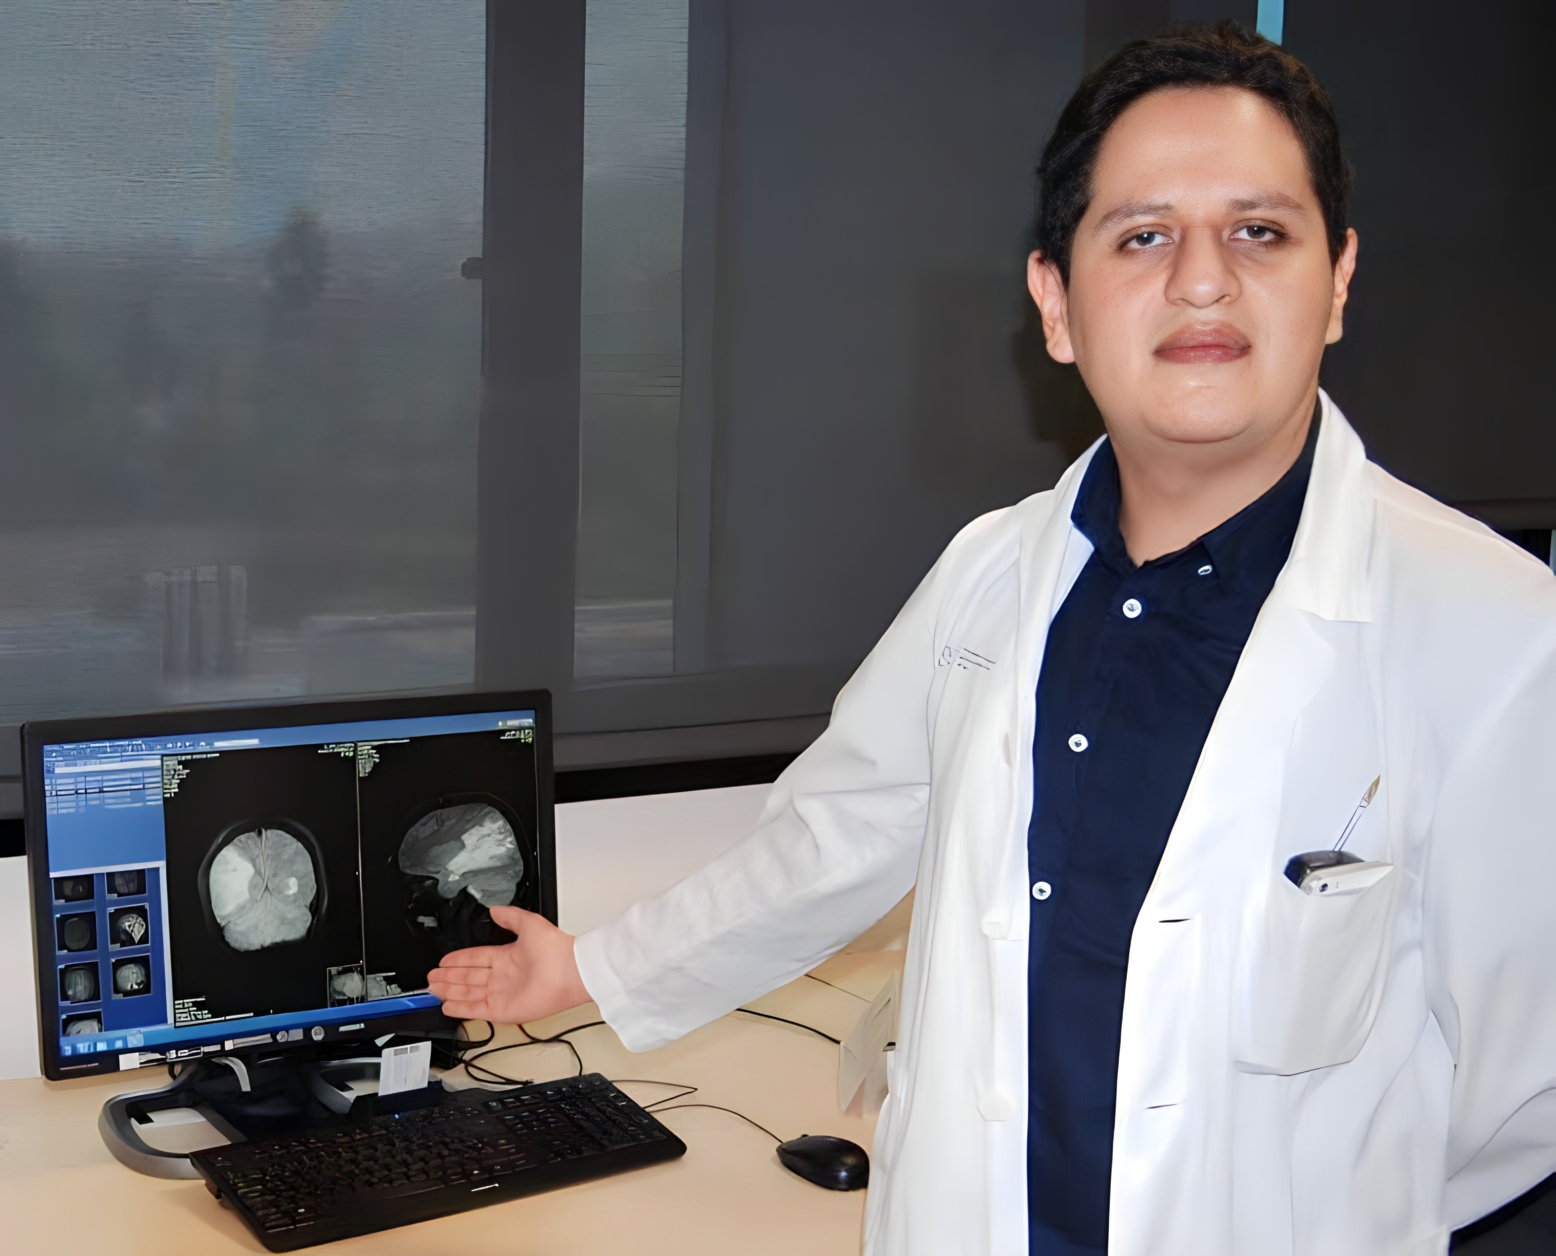

Jose Luis Thenier-Villa, MD, MBI, PhD

Neurosurgeon Specialist

Nacido en Potosí, Bolivia, en 1989, el Dr. José Luis Thenier Villa ha realizado estudios en el grado de Medicina y Cirugía, graduado con honores, ha continuado sus estudios de especialidad en el Hospital Álvaro Cunqueiro de Vigo, actualmente reside y trabaja en Cataluña, donde realiza su actividad asistencial quirúrgica e investigadora.

Especialista en Neurocirugía

Por el Hospital Álvaro Cunqueiro de Vigo, realizando y asistiendo a más de 1000 cirugías en todos los campos de la neurocirugía. Formación en Neurocirugía Pedriátrica y Base Craneal Endoscópica en el Hospital Universitari i Politèctnic La Fe de Valencia. Formación en Neurocirugía de la Epilepsia y Funcional en el Hospital Universitario de Osaka, Japón.